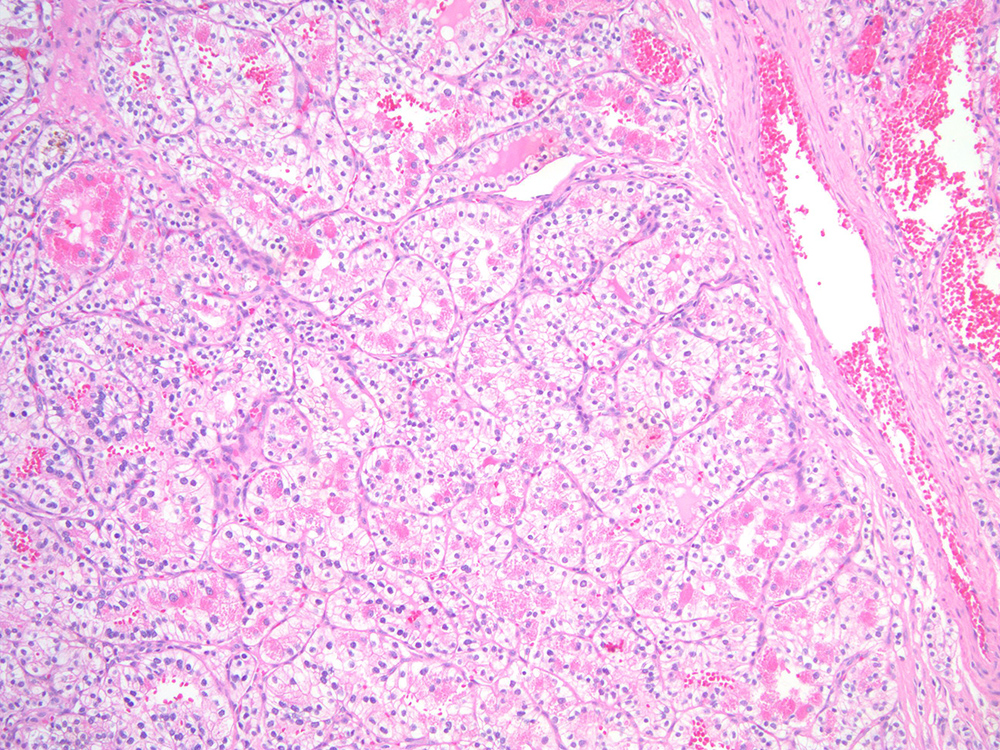

Classification of renal tumors

Case ID: 743